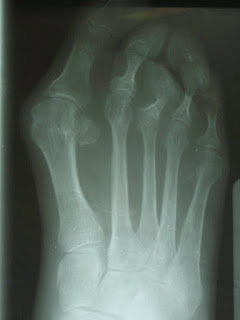

El otro caso, es el primero que cuelga en la página. La paciente tiene un buen chaperón, Hallux Valgus, segundo y cuarto dedos en martillo, tercero en garra e infraductus, 2º y 3º se "besan", sobrecarga en cabeza de 2º meta y luxación en 3ª artic. MTF. Posiblemente me decida por Austin, artrodesis de dedos, osteotomía acortadora de 2º meta o Weill en 2º-3º, osteotomía en V en 2º y Weill en tercero ( espero opiniones).